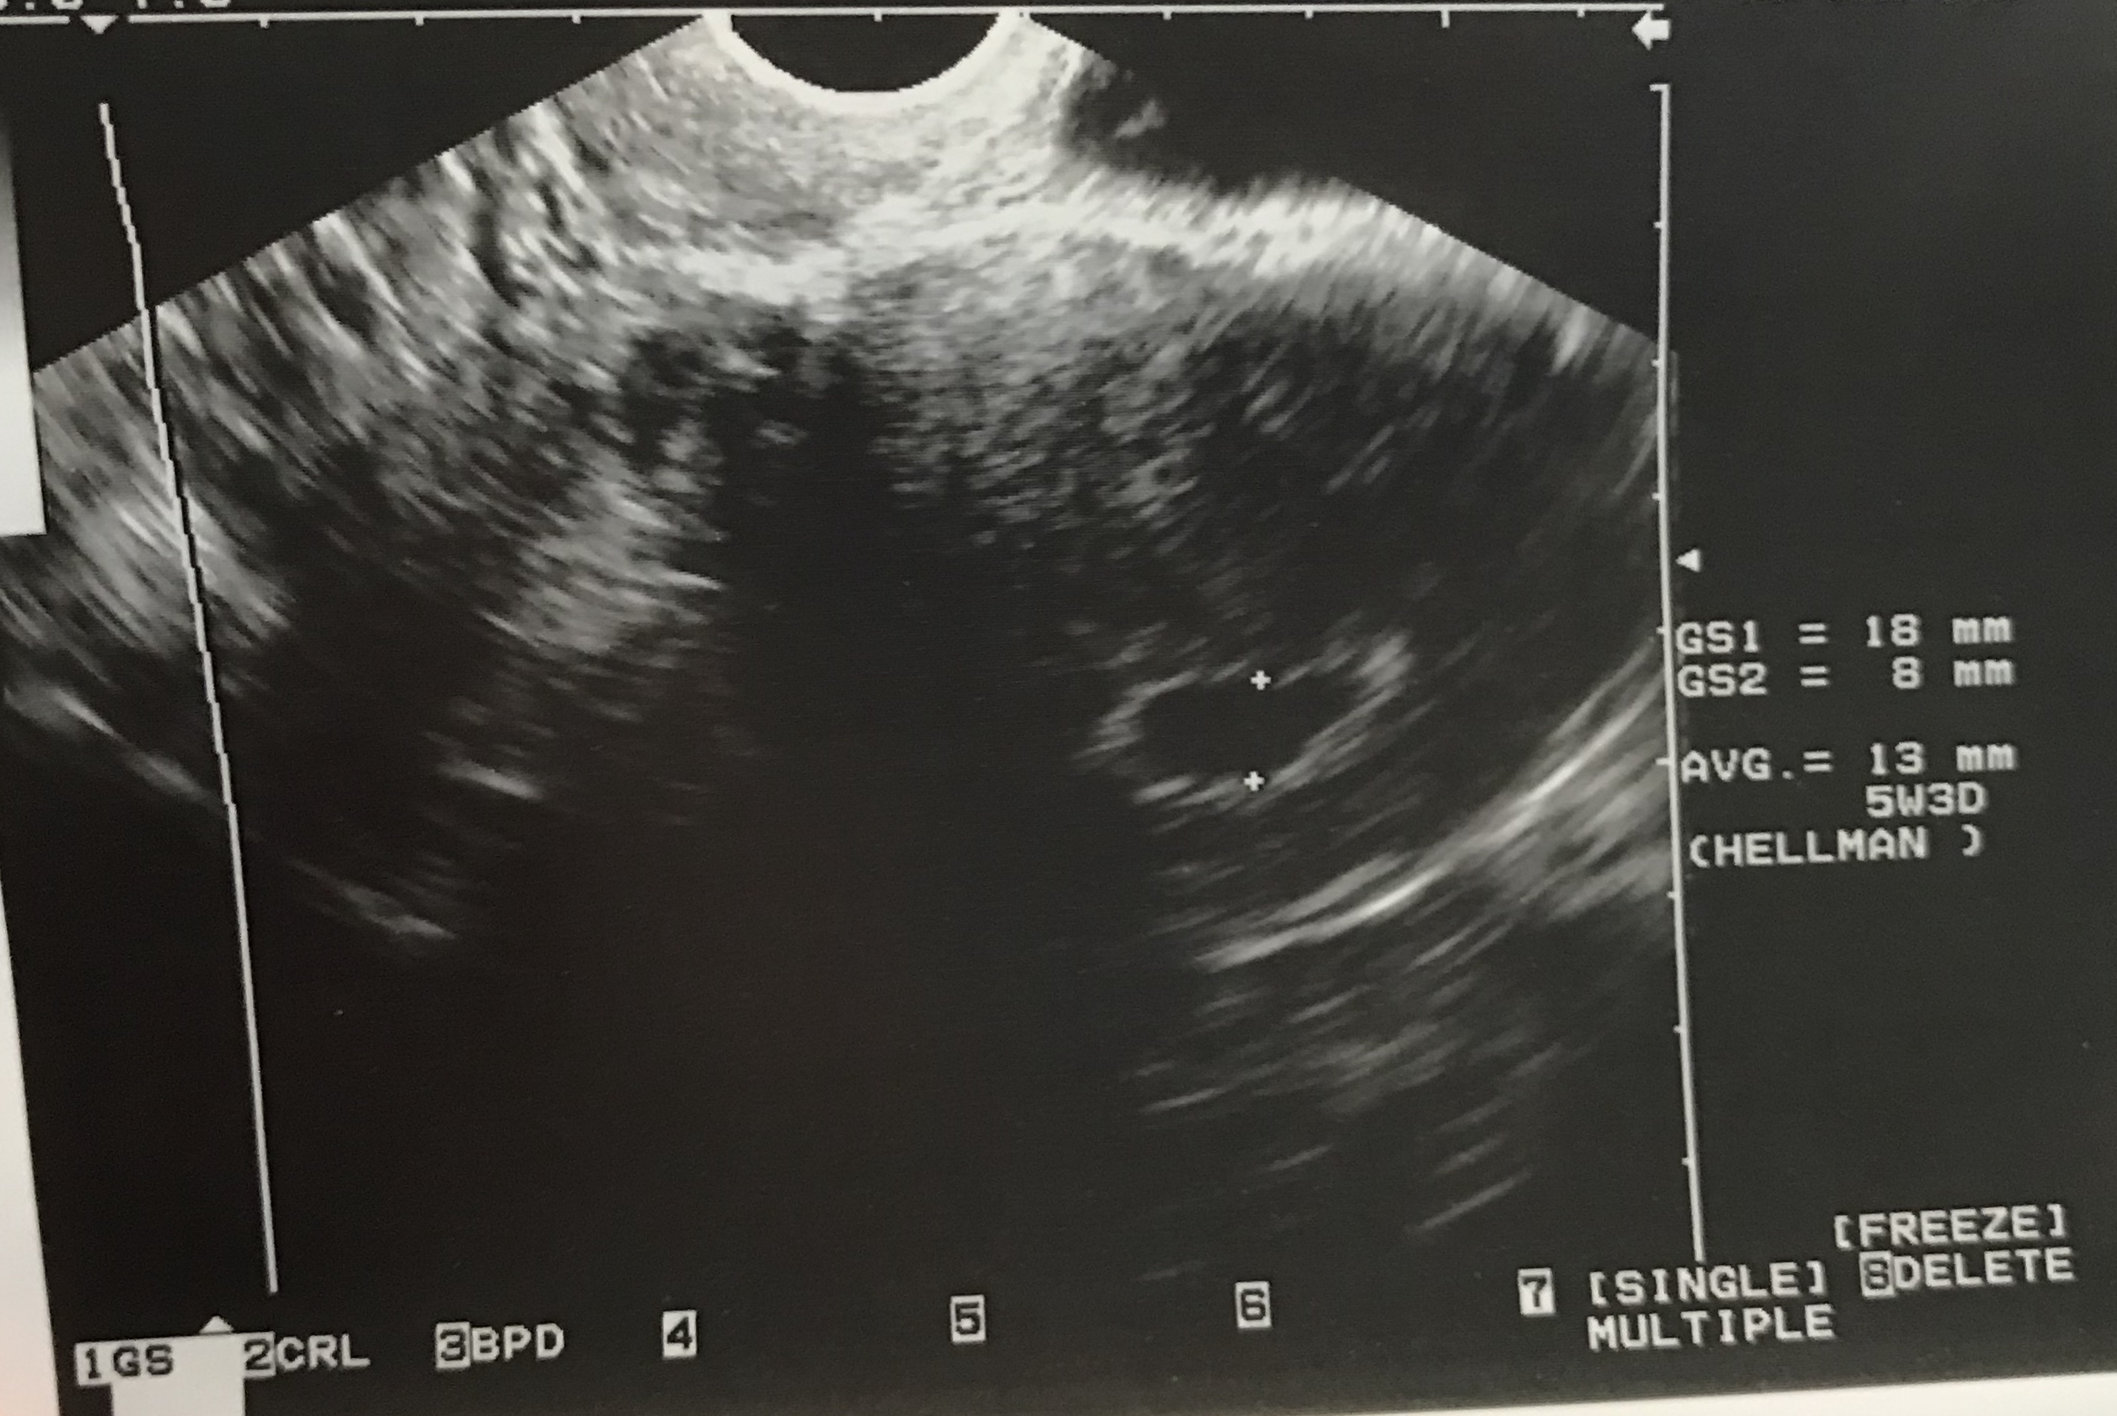

Well I went to my first appointment today and I thought I was 7w2d based on my LMP. Turns out I must have ovulated WAY later then I thought and I’m only 5w3d! He said everything looks totally normal for 5 weeks and he wants me back in 3 weeks to do another ultrasound. I’m so glad that everything looks good, but I’m sad that we couldn’t see baby yet or hear a heartbeat. Gah! I’m nervous and frustrated that I’m back 2 whole weeks. But anyway, here’s a picture of my gestational sac?